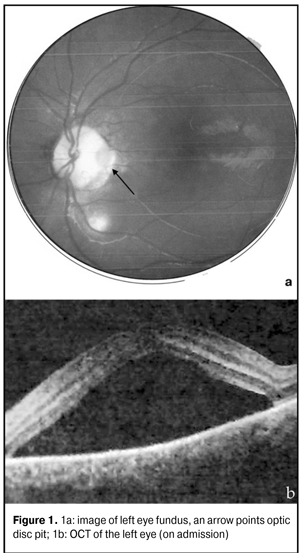

Key words: optic disc pit, serous neuroepithelial detachment, laser coagulation Introduction Optic disk pit has been considered as coloboma located, as a rule, near temporal part of the optic disc [1, 5]. In 50 % of patients develops central serous retinal detachment. However, pathogenesis of the disease is understudied. Some authors have considered optic disc pit as a variant of optic disc hypoplasia with nerve fibre in-growth retardation. Other authors have associated the formation of pits with the insertion of rudimentary retina folders into intervaginal spaces of the optic nerve [2, 5]. Visual acuity is not decreased if there is no complication. The optic disc is slightly larger than the normal one with an oval or round pit, which size is varied within wide ranges. As a rule, the pit is located in the temporal part of the disc, but sometimes it can pe located in the centre. More often than not, visual field defects have been noted and they can resemble alterations in glaucoma. Pathological changes in the macular area are manifested in serous neuroepithelial detachment and usually developed in juvenility. Fluid has been considered to get under the retina from the vitreous body. The possibility of fluid penetration from subarachnoid space of the optic nerve and leakage from abnormal vessels into the base of the tip has also been discussed [3]. First, serous detachment of the inner retinal layers appears. Afterwards, it develops in the outer retinal layers, which is sometimes accompanied by subretinal complications. Herewith, ophthalmoscopic picture observed can resemble central serous chorioretinopathy [3, 9]. Most of all, pits are detected in ophthalmoscopy in a form of dark spots with sharp margins, sized from ? to 1/8 of disc’s diameter, located in the temporal part near the edge and covered with veiling-like grayish tissue [2, 6]. Treatment The initial stage is observation every three months with relation to spontaneous resolution of neuroepithelial detachment occurred in 25 % of cases. If dynamics is absent, afterwards, laser coagulation of the retina can be performed if vision acuity reduces progressively; at that, coagulators are applied along the temporal margin of the disc. The efficacy of such treatment is 23-35 % [3]. If laser coagulation is not effective, gas tamponade vitrectomy and endolaser coagulation are performed. The operation is effective in 50-70 % of cases [3, 5]. The purpose of the present study is to show practically the possibility to use laser coagulation as an entire method for treatment of optic disc pit complicated by serous neuroepithelial detachment in children. In november 2013, a 4 year old patient P. was taken by her parents to the district ophthalmologists with complaints of yellow-green discharge, both eye redness for 3 days. On ocular examination, the patient had vis OD=0.7; OS=0.5. The patient was diagnosed acute conjunctivitis of both eyes and prescribed antibiotics instillation with her 4-day follow-up visit. On ocular reexamination, the visual acuities were OD = 0.7; OS = 0.2. Cycloplegia examination revealed the absence of OS macular reflex (grayish color in the macular area). Congenital abnormality of eye fundus in both eyes was diagnosed. The patient was referred to consultation in Kiev children clinic hospital. There, on ocular examination, the patient was diagnosed optic disc pit (ODP) in both eyes. On the eye fundus: OD, the optic disc was pale-pink with sharp margins and cyst formation at 11 o’clock; OS, whitish sites of damage were noted in the macular area. Optical coherent tomography was performed and the treatment prescribed was 1.0 ml of betamethasone parabulbarly OS No3, 1 injection per day. After corticosteroids treatment, insignificant decrease in height of neuroepithelial detachment was noted; however, uncorrected visual acuity was OS=0.008-0.1. The patient was referred to SI “Filatov institute of Eye Diseases and Tissue Therapy of the NAMS of Ukraine” in Odessa. Condition on admission was vis OD=1.0; OS=0.2=sph-1.0dcyl-0.5dax30°=0.3. In both eyes, the conjunctiva was pale-pink, smooth, and transparent; the cornea was transparent, brilliant and mirror-like. The content of the anterior chamber was transparent; the pupil was round and 2-4 mm in diameter, mobile; the lens was transparent. The optic disc in both eyes was pale-pink with sharp margins and had optic disc pits and peripappilary chorioretinal scarring with pigmentation. Vessels were of a normal caliber. The patient had parquet fundus of the eye. Macular reflex was clear in the right eye and pathological in the left eye; neuroepithelial detachment was revealed at the macula area. Figure 1 of left eye fundus demonstrates optic disk pit with sharp margins at the temporal part between 5 and 6 o’clock. OCT revealed neuroepithelial detachment with a height of 625 mkm (Fig.1).

The patient was diagnosed Jensen’s retinochoroiditis juxtapapillaris in remission with chorioretinal scarring, optic disc pits in both eyes, and serous neuroepithelial detachment in the left eye. The patient was referred to single-discipline specialists to rule out tuberculosis. The results of the investigation are given below. Immunology QuantiFERON – TBTest (for diagnosing latent Mycobacterium tuberculosis infection) – 0.20 IU/ml - negative Ig G Mycobacteriumtuberculosis (enzyme immunoassay (EIA), blood serum) – 2.6 l Eg/ml – negative EIA (autoimmune disease) - antibodies to double-stranded DNA / Ab – 18.59 l Eg/ml – negative Circulating immune complex (CIC) (blood serum) С1q / СIC C1q – 1.75 µm/ml - negative (CIC) (blood serum) C3d / CICC3d- 0.80 µm/ml - negative Ig Е (blood serum) 23.20 IU/ml - negative Bio/immunochemistry Toxoplasma gondii, HSV 1,2, PCRHCV – negative Instrumental tests Multispiral computed tomography of lungs and mediastinum revealed no signs of focal infiltration. Ultrasound investigation (US) of abdominal cavity organs revealed gallbladder volvulus at gallbladder neck. US for thyroid gland revealed no pathological changes. Treatment On August 12, 2015, restrictive laser coagulation was performed in the left eye (laser, 532 nm; 39 laser exposures; power, 110 mW; exposure dose, 150 mc; diameter, 200 µm). Anti-inflammatory and antioxidant treatment was performed postoperatively. Visual acuity on discharge was OD=1.0; OS=0.2=sph -1.0 D = 0.3. On reexamination on December, 12, 2015, uncorrected visual acuity was OD=1.0; OS=0.3. The right eye was stable and the left eye had no inflammation signs, serous neutoepithelial detachment reduced. To rule out unilateral retinitis pigmentosa, dark adaptation test (ОD = 2.85 with a filter; OS = 1.4 without a filter) was performed and followed by grating-like laser coagulation of the retina in the left eye (laser, 532 nm; 87 laser exposures; power, 80 mW; exposure dose, 140 mc; duration скважность – 200 мс; diameter, 200 µm). Anti-inflammatory and antioxidant treatment was performed postoperatively. On her 1 month follow-up visit, the patient had vis OD=1.0; OS=0.5. OCT revealed residual serous neuroepithelial detachment at macular area (Fig. 2). On reexaminations within 2 months, visual acuity was 0.5 in the left eye.